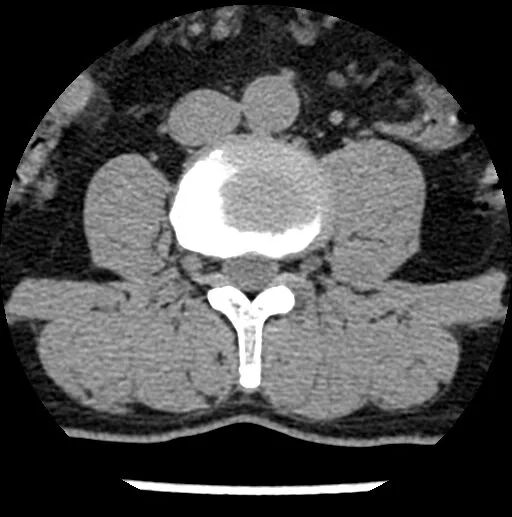

portant; overflow-wrap: break-word !important;">? ? ? ??現(xiàn)病史:患者半年前無(wú)明顯誘因出現(xiàn)腰痛伴左下肢后外側(cè)疼痛、麻木,平臥時(shí)癥狀減輕,坐立及行走時(shí)癥狀明顯,口服營(yíng)養(yǎng)神經(jīng)及鎮(zhèn)痛藥物治療后癥狀減輕。3天前患者癥狀加重,疼痛以左下肢后側(cè)明顯,口服藥物癥狀無(wú)明顯改善,嚴(yán)重影響睡眠、生活。遂于我院門(mén)診就診,行腰椎間盤(pán)CT示:L3/4、L4/5椎間盤(pán)膨出,L5/S1椎間盤(pán)突出并椎管及左側(cè)側(cè)隱窩狹窄?,F(xiàn)為進(jìn)一步診治,門(mén)診以“腰椎間盤(pán)突出癥”收治入院進(jìn)一步治療?;颊咦园l(fā)病以來(lái),飲食可,睡眠治療一般,大小便正常,近期體重?zé)o變化。

術(shù)前影像資料

圖6:術(shù)前CT

圖7:術(shù)前CT